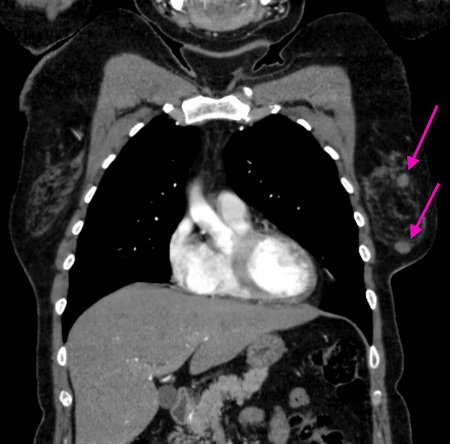

ДИСКОВИДНЫЙ АТЕЛЕКТАЗ ЯЗЫЧКОВЫХ СЕГМЕНТОВ ЛЕВОГО ЛЕГКОГО.

25.11.2015 — КТ грудного отдела с контрастированием:

Слева дисковидный ателектаз язычковых сегментов легкого.

Очаговых, инфильтративных изменений легких не выявлено. Корни структурны. Легочный рисунок не изменен. Диафрагма расположена обычно. Просветы трахеи, главных, долевых, сегментарных бронхов сохранены. Средостенение не расширено, не смешено. Увеличения лимфатических узлов средостения и корней лёгких не отмечено. Надключичные, подмышнчные лимфоузлы не увеличены. Плевра не изменена. Границы сердца не расширены. В полости перикарда выпот не определяется. Лёгочные артерии контрастируются равномерно. Мягкие ткани грудной клетки не изменены. Костных деструктивных изменений не выявлено.

Зпаключение: очагов неопластического процесса в органах грудной полости не выявлено.